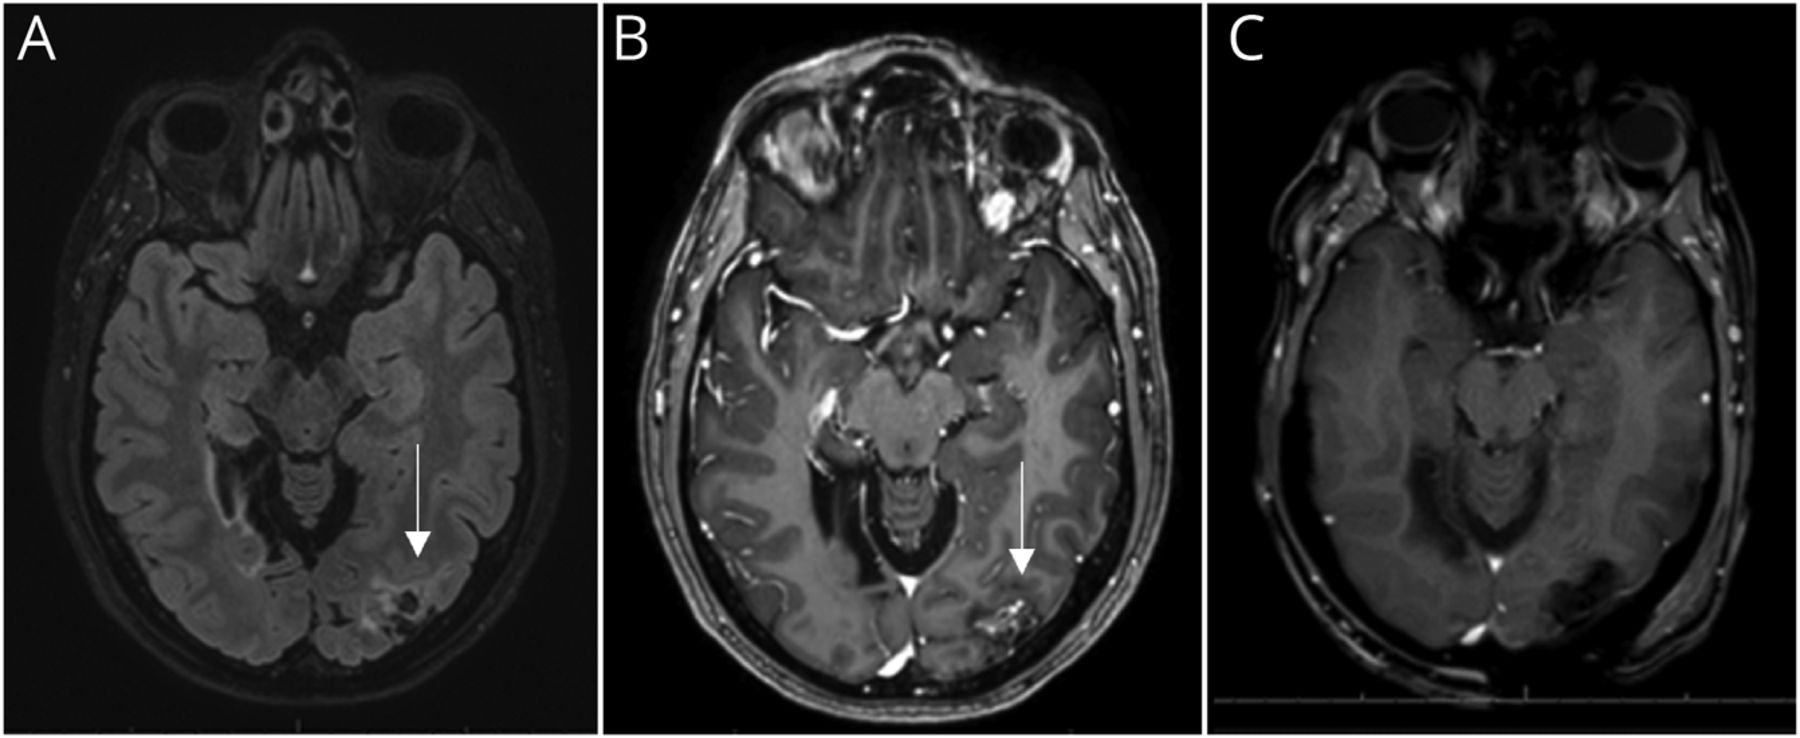

术前和术后MRI。(A)术前轴T2 fluid-attenuated反转恢复和(B)术前轴与对比说明提高病变T1(箭头所指)在左侧枕叶与周围水肿。(C)术后轴T1与对比展示总计切除。